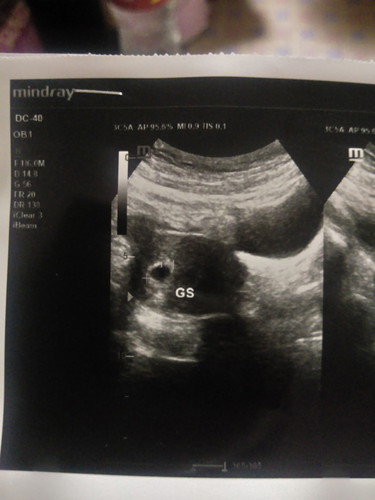

ก่อนรู้ว่าตั้งครรภ์มีอาการเวียนหัวมากๆ เวียนทุกวันและเจ็บหัวนมมาก จนสงสัยว่าตัวเองท้อง เลยตรวจ เจอ 2 ขีด และไปฝากครรภ์ตอน 4 W พอหลังจากนั้นไปมีเลือดออกตอน 5 w 3 d ไปหาหมอ หมอบอกเจอถุงตั้งครรภ์และมีภาวะแท้งคุกคาม พอหลังจากนั้นมาจนถึงตอนนี้ 8 สัปดาห์ 4 วันแล้วอาการแพ้ท้องทุกอย่างหายไปหมด เหมือนคนปกติทุกอย่าง มีแค่หัวนมที่มีการเปลี่ยนแปลง ใหญ่ขึ้น หมอนัดซาวอีกที 30 ตุลานี้ มีแม่ๆคนไหนอาการแพ้ท้องหายไปมั้งค่ะ ?